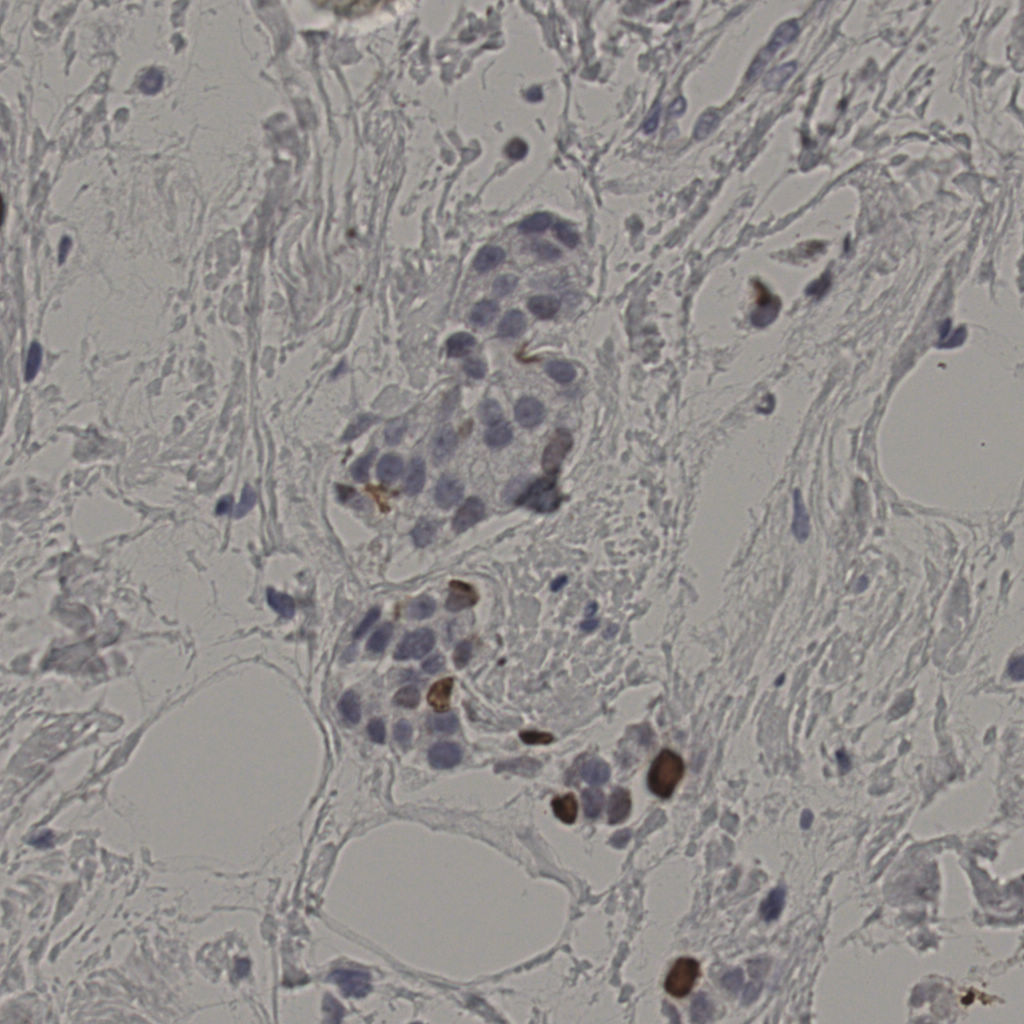

5.31%

Ki67 指数

阴 19502 阳 1093